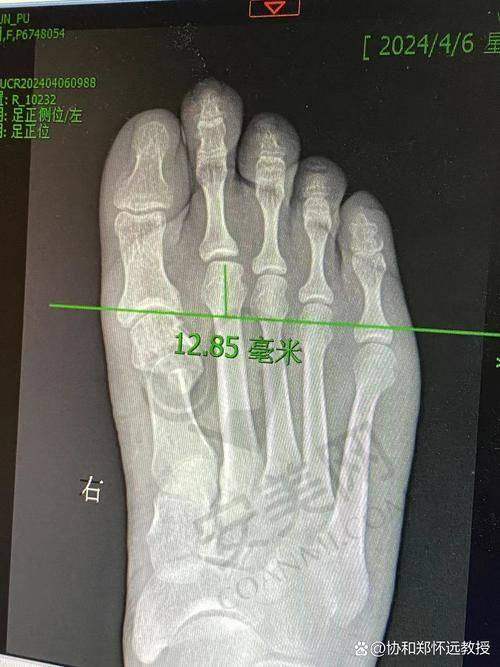

起初,特别多患者和曾经的海淀张大姐一样,心里会嘀咕:苏敬达医生在哪个医院坐诊其实并不是更重要的,关键是他得真有本事。经过一番了解才知道,苏敬达医生毕业于河北医 科 大学,是一位博士。他研发的拇外翻微创器械获得了六项专项,实力不容小觑。

苏医生擅长的“微孔祛大脚骨”技术,与传统骨科手术相比,有三大显著优势。首先,手术切口非常小,只有3.5毫米,而传统手术的切口通常在5厘米以上。其次,该技术不用打钢钉钢板,而是依靠榫卯结构来固定骨头。末尾,术后患者立刻就能走路,张大姐就亲眼看到有姑娘自己走出手术室。

小区退休的王大爷就是一个典型的例子。他十年前在国有医院做过传统的拇外翻手术,没想到去年病情复发,而且更加重度,找到苏敬达医生坐诊的医院时,他的脚趾都已经歪成麻花了。苏医生为他做了三维重建后,采用环V型截骨术进行治疗。如今,王大爷天天都能在紫竹院公园暴走两万步,修复得非常好。